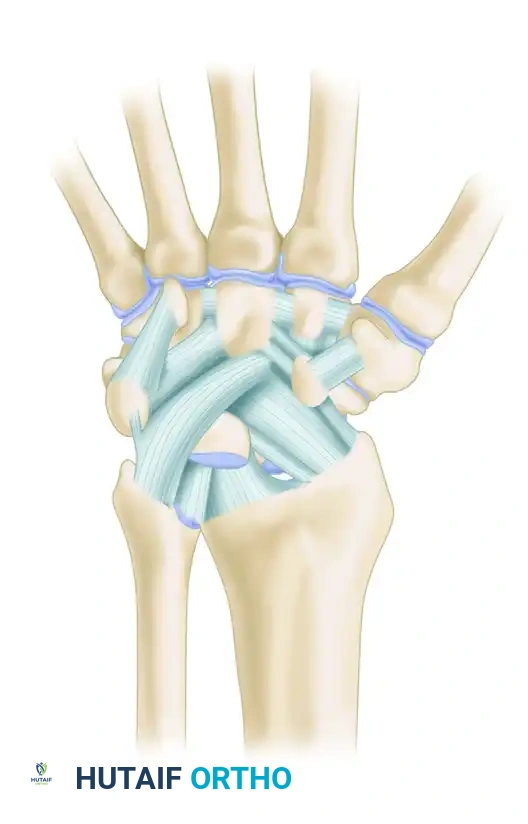

A profound understanding of DRUJ kinematics is requisite for successful surgical intervention. The TFCC is a complex, three-dimensional structure comprising the articular disc, the dorsal and palmar radioulnar ligaments, the meniscus homologue, the ulnocarpal ligaments (ulnolunate and ulnotriquetral), and the extensor carpi ulnaris (ECU) subsheath.

Figure A: Approach to the TFCC, demonstrating the reflection of the dorsal radioulnar ligament and periosteum over the lunate fossa to expose the radial footprint.